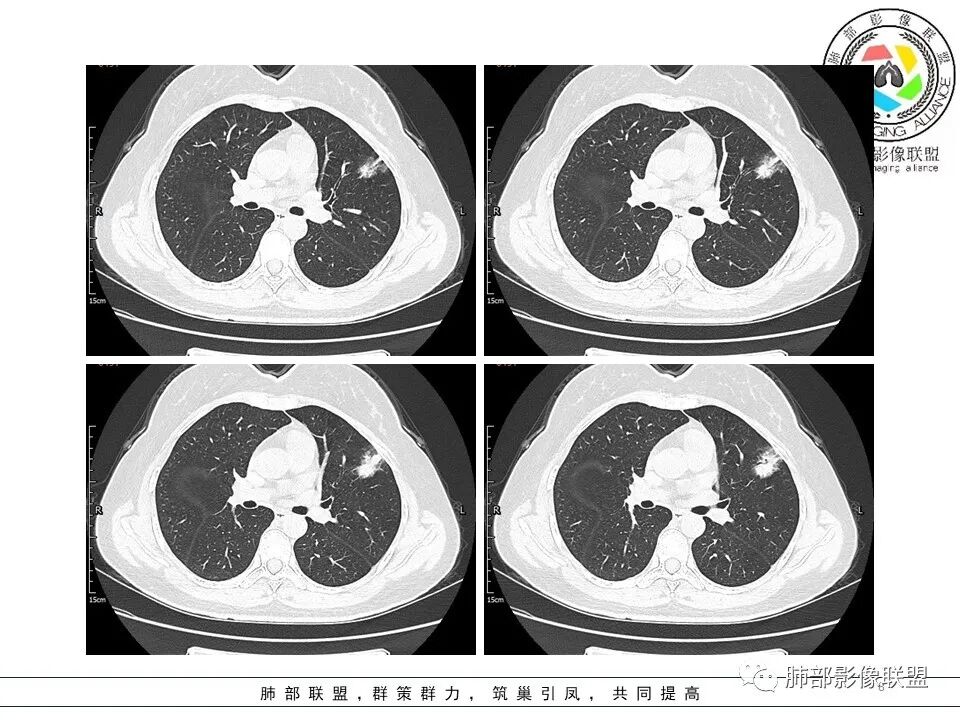

分叶结节,内部结构杂乱,边缘板刷样毛刺,GGO边界清楚

胸膜牵拉

月牙铲?

常规要考虑腺癌

一般半年无变化,边缘GGO

GGO的形成主要由:炎性渗出、出血、肿瘤侵犯

出血,半年会变化,炎性渗出也会变化

当然还有就是纤维化病变可以表现GGO

但是纤维化病变,边缘收缩,条带状为主

按理慢性炎性病变,比较特异性的——结核要放待排,因为结核是妖

左肺上叶胸膜下不规则结节影,分叶、粗短毛刺,胸膜牵拉等,像个“刺头”。

未见钙化,也未显示液化坏死或空洞。

1.病灶周围向几个方向膨出的边界清楚的磨玻璃影,这些磨玻璃影时隔几个月依然,几乎可以排除出血及一般的炎性改变。

2.病灶的胸膜牵拉线与其间病灶胸膜侧的磨玻璃边构成朝向胸壁的“月牙铲”结构,这种影像学表现某种程度上反映出病理学特征——病灶收缩+小叶间隔阻挡。